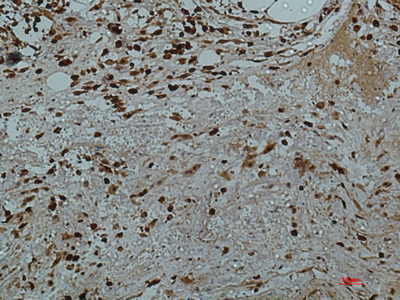

IHC (Immunohistochemisry)

(Immunohistochemical analysis of paraffin-embedded human-colon2 using antibody diluted at 1:50.)